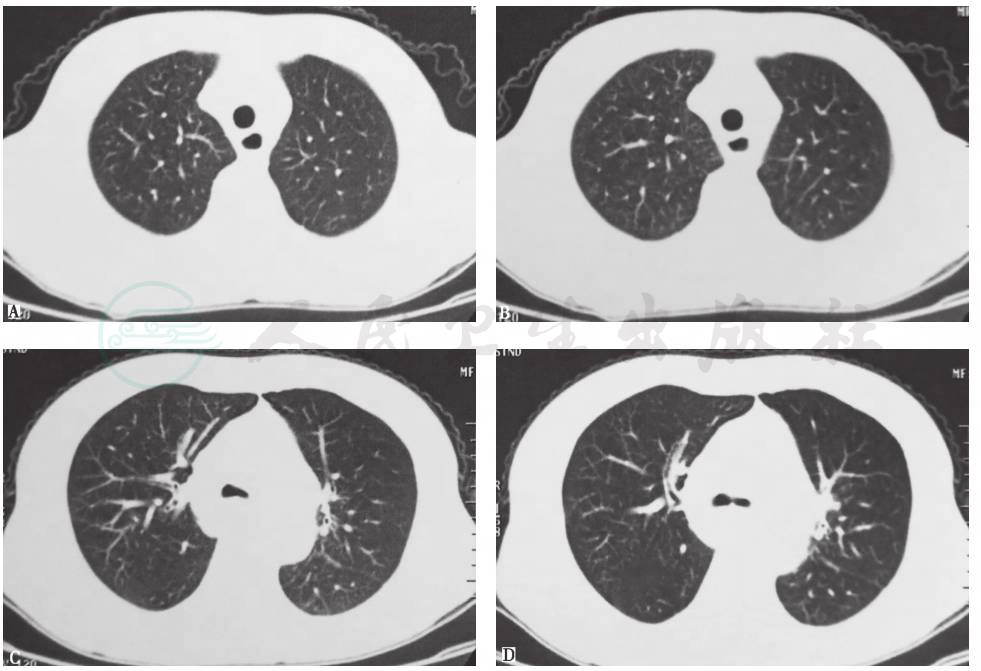

【胃镜检查】

胃镜检查,镜下见慢性活动性炎症病变,溃疡形成,肉芽组织增生,食管-气管瘘,提示食管纵隔肿物(图5)。

活检病理结果:食管多发溃疡,食管壁增厚,周边鳞状上皮乳头状瘤样增生(图6);食管纵隔送检物均为坏死物,未见组织结构(图7)。

图5 胃镜检查镜下所见(2015-03-02)

A.球部;B.胃窦;C.胃底;D、E、F.食管